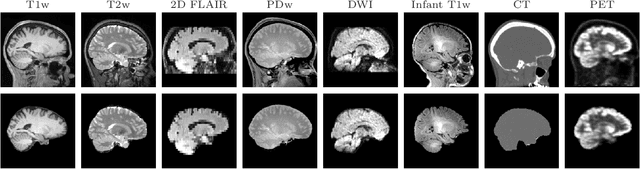

Abstract:The removal of non-brain signal from magnetic resonance imaging (MRI) data, known as skull-stripping, is an integral component of many neuroimage analysis streams. Despite their abundance, popular classical skull-stripping methods are usually tailored to images with specific acquisition properties, namely near-isotropic resolution and T1-weighted (T1w) MRI contrast, which are prevalent in research settings. As a result, existing tools tend to adapt poorly to other image types, such as stacks of thick slices acquired with fast spin-echo (FSE) MRI that are common in the clinic. While learning-based approaches for brain extraction have gained traction in recent years, these methods face a similar burden, as they are only effective for image types seen during the training procedure. To achieve robust skull-stripping across a landscape of protocols, we introduce SynthStrip, a rapid, learning-based brain-extraction tool. By leveraging anatomical segmentations to generate an entirely synthetic training dataset with anatomies, intensity distributions, and artifacts that far exceed the realistic range of medical images, SynthStrip learns to successfully generalize to a variety of real acquired brain images, removing the need for training data with target contrasts. We demonstrate the efficacy of SynthStrip for a diverse set of image acquisitions and resolutions across subject populations, ranging from newborn to adult. We show substantial improvements in accuracy over popular skull-stripping baselines - all with a single trained model. Our method and labeled evaluation data are available at https://w3id.org/synthstrip.